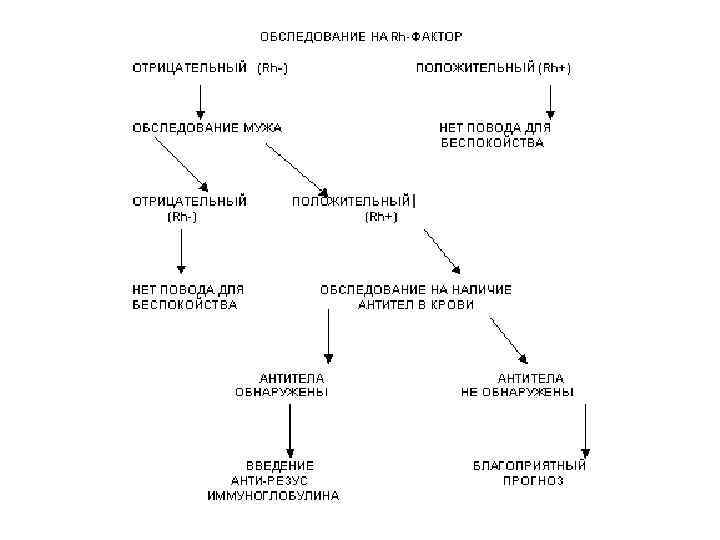

Вопрос 11 Система резус (Rh-hr)

Вопрос 11 Система резус (Rh-hr)